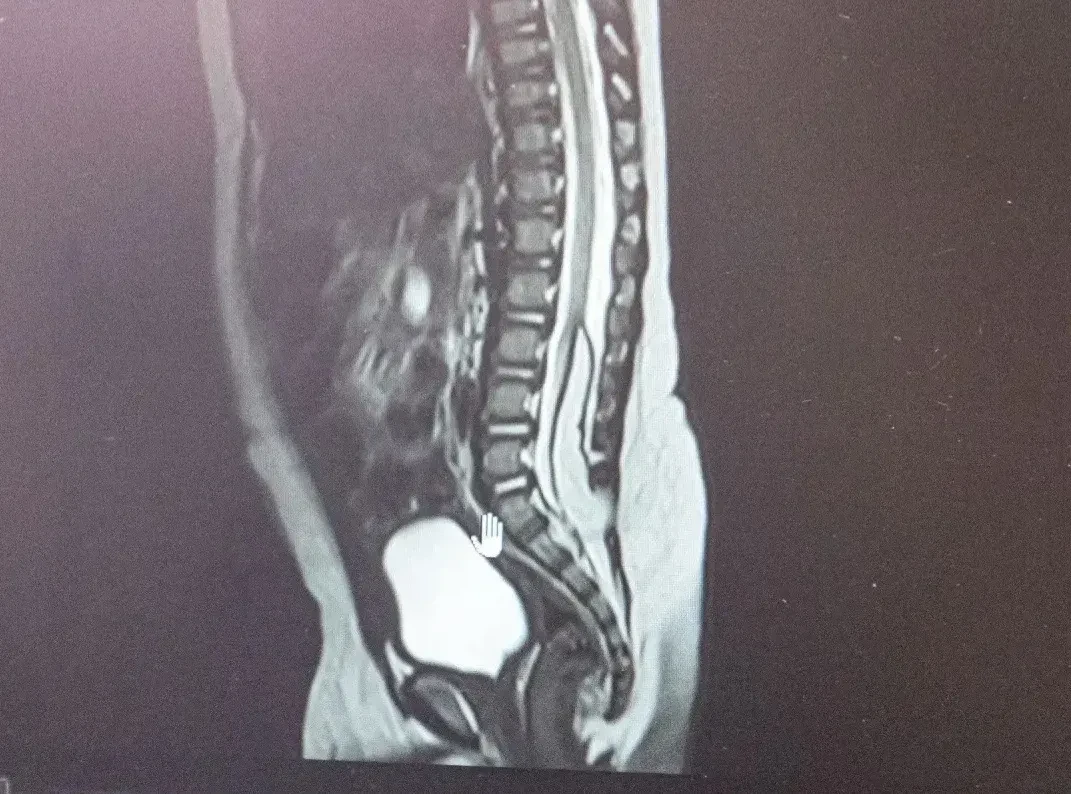

С начала года у детей 6 и 8 месяцев выявили липомиелоцеле. При таком врожденном пороке развития центральной нервной системы патологическая жировая ткань образуется в спинном мозге, фиксируя его и нарушая развитие и рост. Как отметили в областном Минздраве, липомиелоцеле чревато нарушением работы тазовых органов и недержанием.

Кемеровские нейрохирурги с помощью ювелирно проведенных операций удалили новообразования.